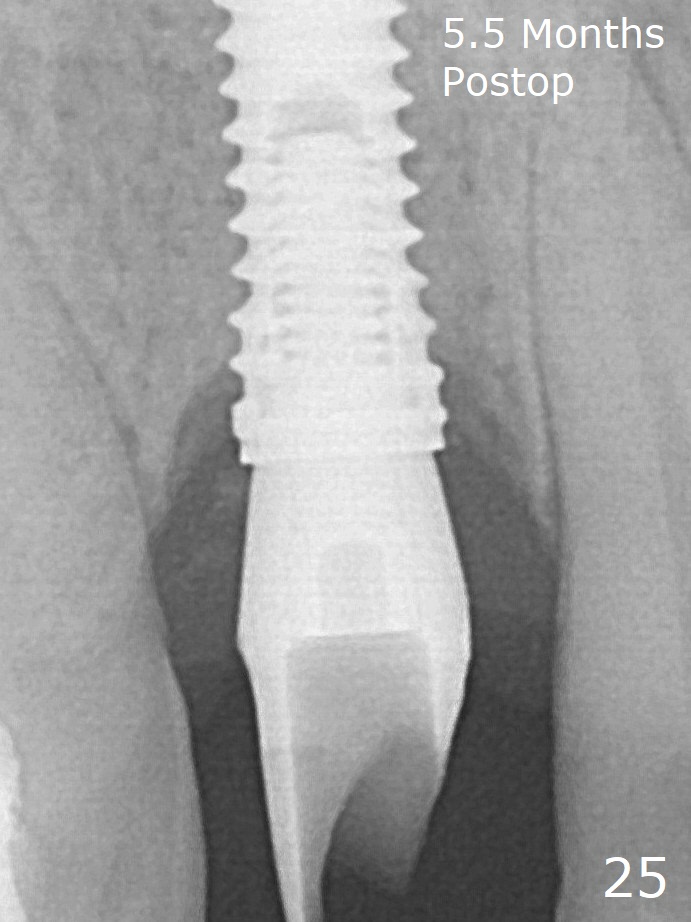

Finally using Lindamann bur, the osteotomy is changed so that a 3.5x13 mm 2-piece implant does not need an angled abutment to establish occlusion (Fig.19). There is one palatal thread exposure. Allograft is placed circumferentially, followed by Human Amnion-Chorion Allograft and Collagen Plug. A 4.5x5.5(3) mm appears to be seated incompletely with a gap between the abutment and the implant (Fig.24 <, overtightened?). A provisional is fabricated after heavy palatal reduction. Two months later, the provisional fractures. After repositioning the abutment with complete seating and torque (Fig.25), impression is taken.